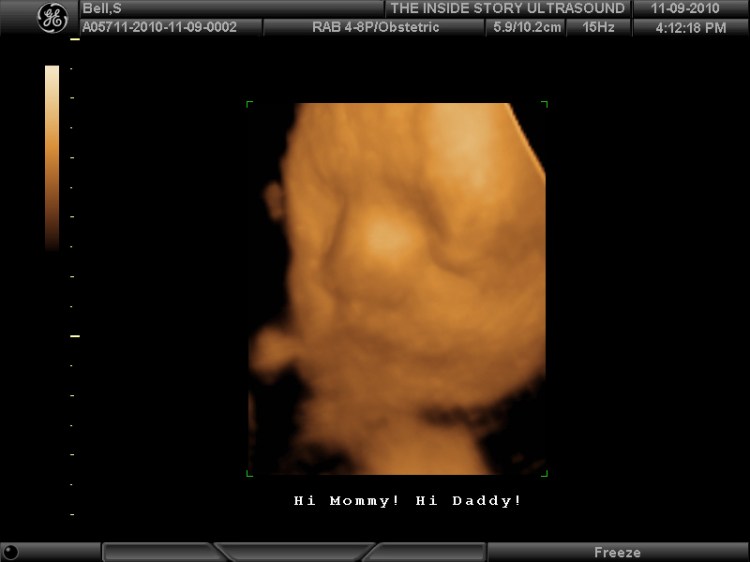

Ultrasonidos 3D: para los ultrasonidos 3D, se toman múltiples imágenes bidimensionales en varios ángulos y luego se ensamblan para formar una representación tridimensional. Por ejemplo, en lugar de solo ver una vista de perfil de la cara de tu belleza, en un sonograma 3D puedes ver toda la superficie (se parece más a una foto normal).

Ultrasonidos 4D: un ultrasonido 4D es similar a un ultrasonido 3D, pero la imagen muestra el movimiento como lo haría un video. Entonces, en una ecografía 4D, vería a su bebé haciendo cosas en tiempo real (como abrir y cerrar los ojos y chuparse el dedo).